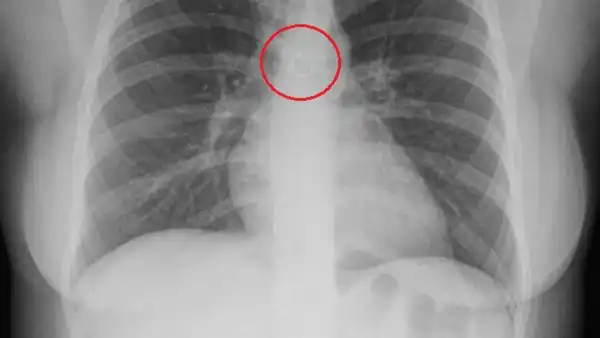

In her shared videos, she disclosed that the errant jewelry was positioned a mere 0.5 millimeters from her aorta, as reported by Jam Press.

The nose ring was precariously situated near her aorta, the body’s main artery. (Jam Press)